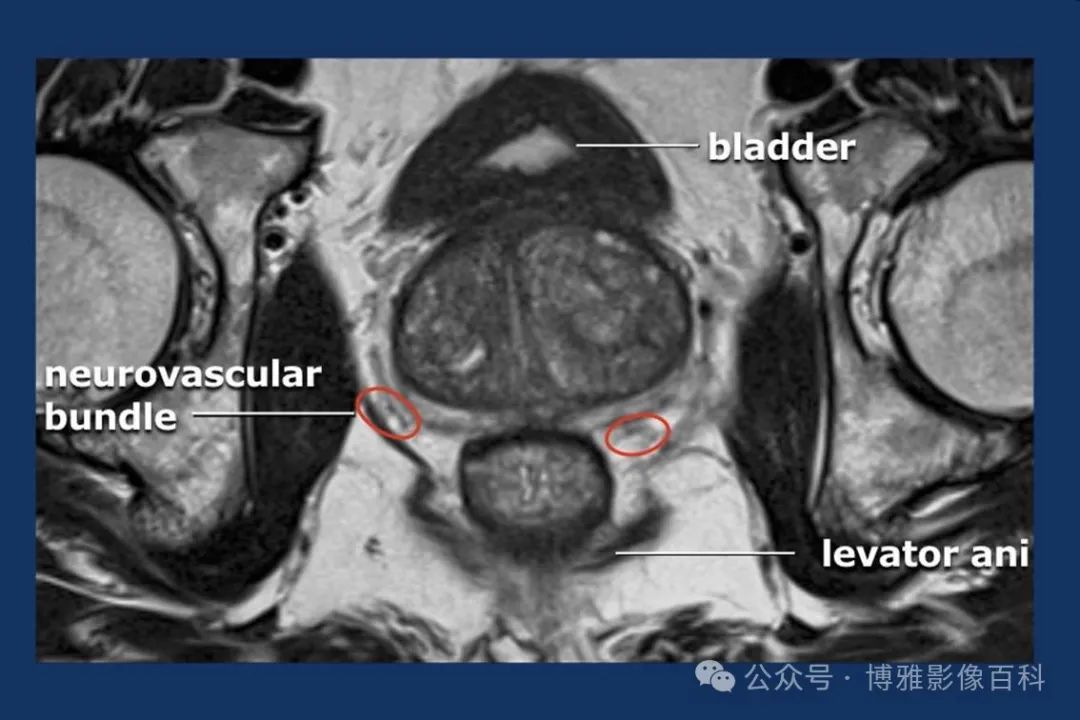

MR 解剖学

前列腺良性增生患者的轴向T2 图像,其他方面正常。外周带是一薄层均匀的高信号,边界清晰连续性的低信号包膜。移行带通常表现为不均匀中等信号,病灶被边界清楚的BPH良性前列腺增生结节所取代。精囊具有均匀T2高信号。未见淋巴结肿大。